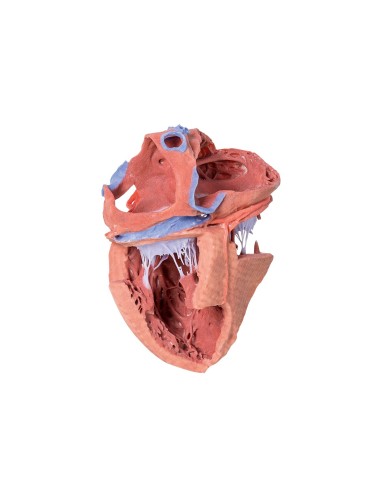

I modellini anatomici di cuore umano sono strumenti indispensabili per uno studio corretto dell'anatomia del cuore umano.

Fra i modelli di base segnaliamo il modello di cuore classico in due parti, in cui le due metà del cuore sono tenute insieme da potenti magneti.

Per una migliore comprensione delle strutture anatomiche del cuore sono stati realizzati anche dei modelli anatomici di cuore ingrandito, si va dai piccoli ingrandimenti fino ai modelli di cuore per la formazione in aula, come il modello anatomico di cuore gigante prodotto da 3B Scientific: un modello di cuore ingrandito di ben otto volte.

Su Tuttoanatomia trovi la più vasta selezione online, certamente abbiamo il modello di cuore più adatto alle tue esigenze. I cardiologi e gli studenti acquistano i modelli anatomici di cuore umano per studiare nei minimi dettagli la struttura anatomica del cuore umano, ma anche per dare spiegazioni ai propri pazienti, per illustrare visivamente la patologia di cui sono affetti, ed il tipo di intervento che si intende eseguire durante la terapia. Le quotazioni su Tuttoanatomia sono le più convenienti del mercato e la qualità dei prodotti è davvero eccezionale, in modo da offrirti un rapporto qualità prezzo incomparabile.